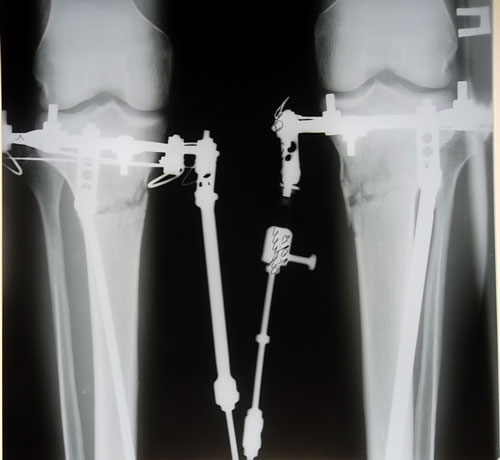

Поглядите на мои ровные ножжжки)) я вообще доволен результатом!)) Спасибо Николаю Николаевичу!

Сергуня, не ножки, а загляденье! Поздравляю с отличным результатом!Sergunya писал(а):Поглядите на мои ровные ножжжки)) я вообще доволен результатом!)) Спасибо Николаю Николаевичу!

Смотрю подмерзать стал-носочки одел. Палочки получились ровные. Теперь смело можешь вставать на ворота.